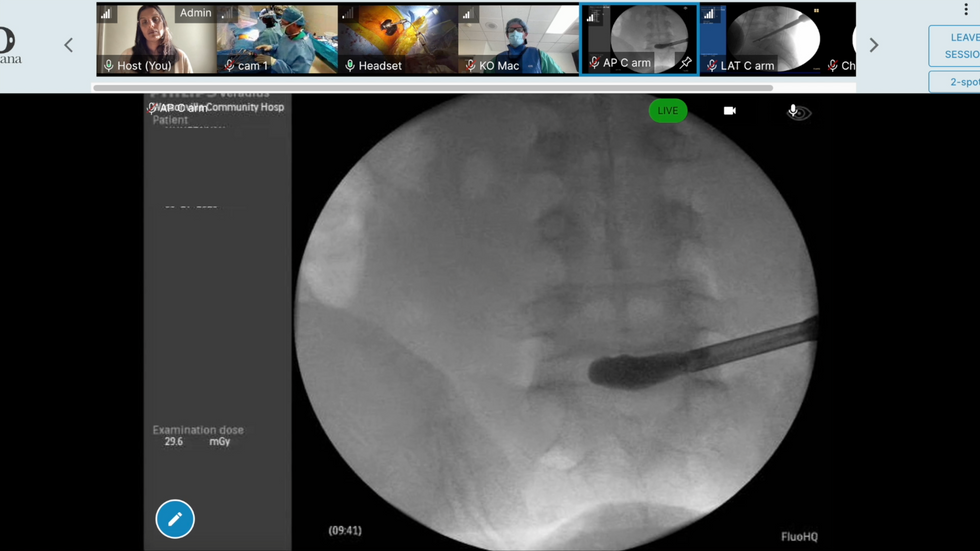

The software needed to integrate with various intraoperative imaging systems like C-Arm and O-Arm while providing accurate, real-time feedback.

Solution

We developed robust APIs and imaging mirroring capabilities that allowed Orcana MARSTM to interface seamlessly with existing medical hardware, ensuring precise visualization for both in-person and remote users.

Well Played Studios partnered with Orcana to design and develop the cutting-edge software for their telepresence platform, Orcana MARSTM. Leveraging our expertise in augmented reality and immersive technology, we collaborated closely with Orcana’s team to create a secure, OR-specific solution that integrates seamlessly with intraoperative imaging systems such as C-Arm and O-Arm. Our work focused on enabling real-time, first-person point-of-view collaboration, gesture detection, and advanced image processing to enhance surgical precision and remote support. Together, we brought Orcana’s vision of transforming remote medical collaboration and image-guided surgery into a powerful, user-friendly reality.

Well Played Studios’ collaboration with Orcana on the development of their Orcana MARSTM platform proved to be a success. The platform was instrumental in facilitating real-time augmented reality collaboration and advanced imaging integration during the height of COVID-19 protocols, which restricted medical representatives from entering operating rooms. Orcana MARSTM was successfully utilized in numerous spinal surgeries across California, enabling remote experts to provide crucial guidance and support while maintaining sterile environments and ensuring patient safety.